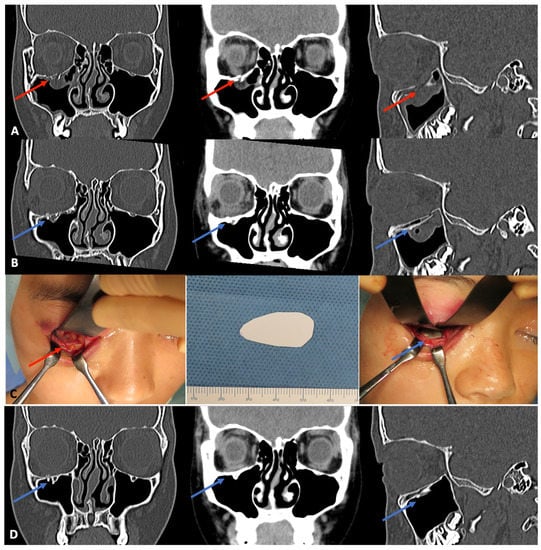

3.1.1. Orbital Wall Fractures

- Tsumiyama, S.; Umeda, G.; Ninomiya, K.; Miyawaki, T. Use of Unsintered Hydroxyapatite and Poly-L-lactic Acid Composite Sheets for Management of Orbital Wall Fracture. J. Craniofac. Surg. 2019, 30, 2001–2003. [Google Scholar] [CrossRef] [PubMed]

- Kohyama, K.; Morishima, Y.; Arisawa, K.; Arisawa, Y.; Kato, H. Immediate and long-term results of unsintered hydroxyapatite and poly L-lactide composite sheets for orbital wall fracture reconstruction. J. Plast. Reconstr. Aesthet. Surg. 2018, 71, 1069–1075. [Google Scholar] [CrossRef] [PubMed]

- Watanabe, A.; Yamanaka, Y.; Rajak, S.N.; Nakayama, T.; Ueda, K.; Sotozono, C. Assessment of a Consecutive Series of Orbital Floor Fracture Repairs With the Hess Area Ratio and the Use of Unsintered Hydroxyapatite Particles/Poly l-Lactide Composite Sheets for Orbital Fracture Reconstruction. J. Oral Maxillofac. Surg. 2021, 79, 420–428. [Google Scholar] [CrossRef]

- Kanno, T.; Karino, M.; Yoshino, A.; Koike, T.; Ide, T.; Tatsumi, H.; Tsunematsu, K.; Yoshimatsu, H.; Sekine, J. Feasibility of Single Folded Unsintered Hydroxyapatite Particles/Poly-L-Lactide Composite Sheet in Combined Orbital Floor and Medial Wall Fracture Reconstruction. J. Hard Tissue Biol. 2017, 26, 237–244. [Google Scholar] [CrossRef]

- Kanno, T.; Tatsumi, H.; Karino, M.; Yoshino, A.; Koike, T.; Ide, T.; Sekine, J. Clinical Report: Applicability of an Unsintered Hydroxyapatite Particles/Poly-L-Lactide Composite Sheet with Tack Fixation for Orbital Fracture Reconstruction. J. Hard Tissue Biol. 2016, 3, 329–334. [Google Scholar] [CrossRef]

- Dong, Q.N.; Karino, M.; Koike, T.; Ide, T.; Okuma, S.; Kaneko, I.; Osako, R.; Kanno, T. Navigation-Assisted Isolated Medial Orbital Wall Fracture Reconstruction Using an U-HA/PLLA Sheet via a Transcaruncular Approach. J. Investig. Surg. 2020, 33, 644–652. [Google Scholar] [CrossRef] [PubMed]